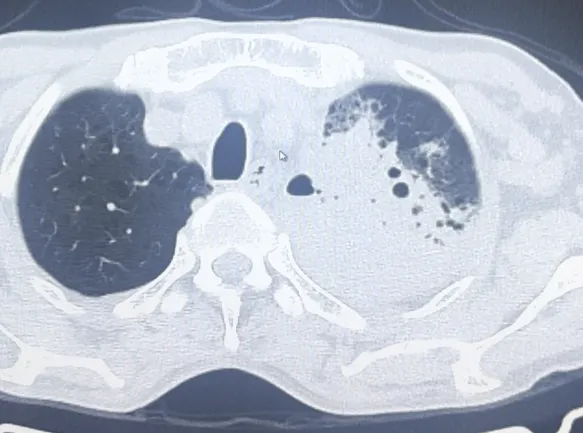

患者王大爷,因出现反复咳嗽、咳痰、喘促症状,入院后经查胸部ct显示左肺占位性病变,但病理性质未明确。为明确病变性质,经与患者及家属沟通同意并充分评估后,医学影像科熊江主任决定行CT引导下经皮肺穿刺活检术,明确肺部病灶性质,为指导下一步诊治提供充分依据。

2.CT扫描,制定穿刺路径,以精确定位穿刺点位置、角度、深度。

3.充分局部麻醉,采用专用活检针进行穿刺,获得1-3条肺部病变组织进行病理分析/病原菌培养。